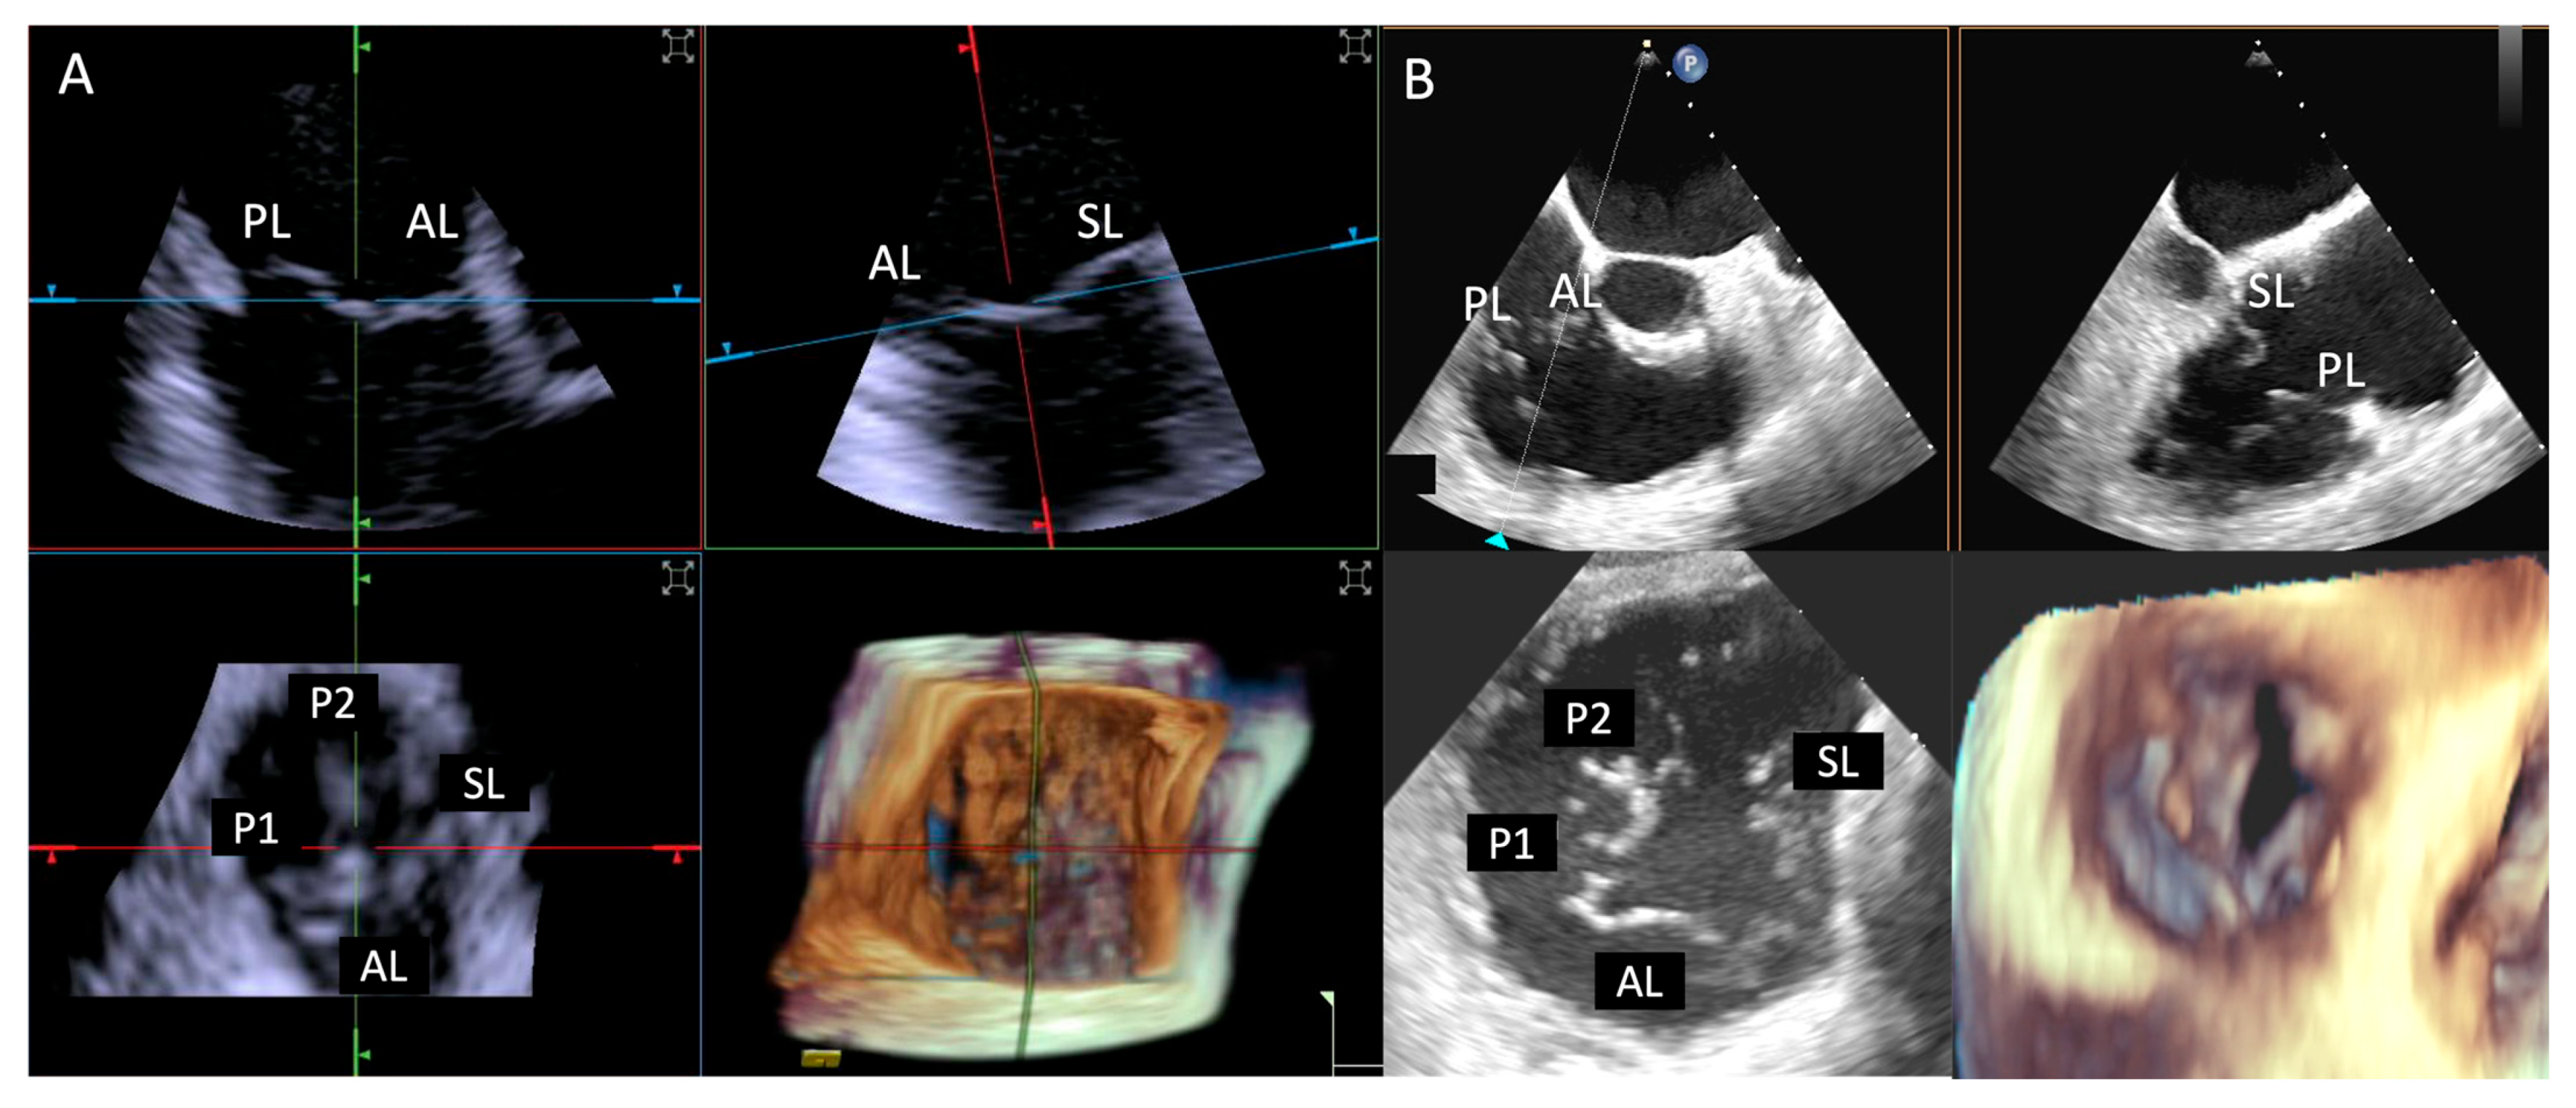

- Step number 1: assessment of tricuspid valve anatomy.

- Step number 2: identification of the target lesion.